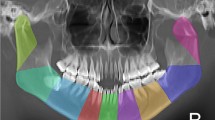

AI can execute different tasks, ranging from searching the web to self-driving cars—tasks that until a few years ago could only be performed by humans. Deep learning (DL) is a subset of machine learning (ML) that uses mainly convolutional neural networks (CNNs) [4]. CNNs are combinations of artificial neuron layers with different units. These units operate like neurons of our brain [3]. CNNs can learn to recognize discriminative features from data and assign importance to various aspects in the image and to differentiate one from another. An example of data used to train an ankle fracture CT CNN is presented in Supplemental Video 1. While most earlier AI methods have led to applications with subhuman performance, recent CNNs are able to match and even surpass the capacity of humans detecting certain fractures on radiographs, focusing on isolated fracture types per model [5,6,7,8,9]. The strength of computers is their ability to evaluate a vast number of examinations rapidly, consistently and without exhaustion.